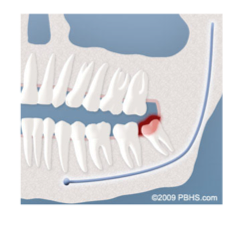

Infection:

The most frequent clinical problem we see is pericoronitis, (a localized gum infection). Without enough room for total eruption, the gum tissue around the wisdom tooth can become irritated and infected, resulting in recurrent pain, swelling, and problems with chewing and/or swallowing.